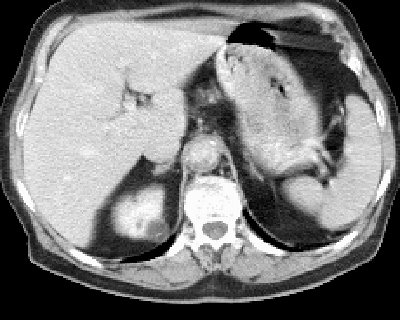

Первым из критериев, заставляющих отнести образование ко II категории, является визуализация стенки кисты при УЗИ и/или КТ (рис. 6, 7).

а) До внутривенного контрастирования (определяется выбухание латерального контура левой почки, подозрительное на новообразование).

б) После контрастирования (образование по латеральному контуру не изменяет плотность и становится гиподенсивным по отношению к паренхиме почки; парапельвикальные кисты не накапливают контрастный препарат).

Компьютерная томография. В правой почке в среднем сегменте определяется гомогенное образование с четкими контурами, округлой формы, равномерно пониженной плотностью +6 HU по шкале Хаундсвильда, диаметром до 60 мм. Признаки капсулы отсутствуют, киста четко отделена от нормальной паренхимы. После введения контрастного вещества образование не изменяет свои размеры, форму и плотность. В полости образования определяется солитарная перегородка, толщиной до 1 мм, которая при контрастировании накапливает контраст.

Заключение: Киста правой почки среднего сегмента II категории (рис. 9).